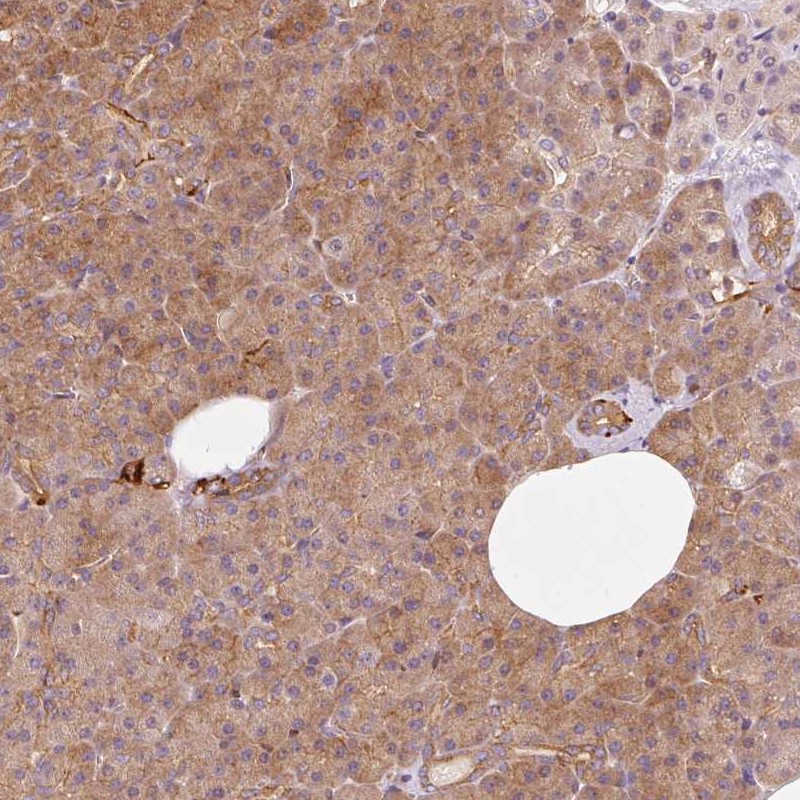

Immunohistochemical staining of human pancreas shows distinct cytoplasmic and membranous positivity in exocrine glandular cells.